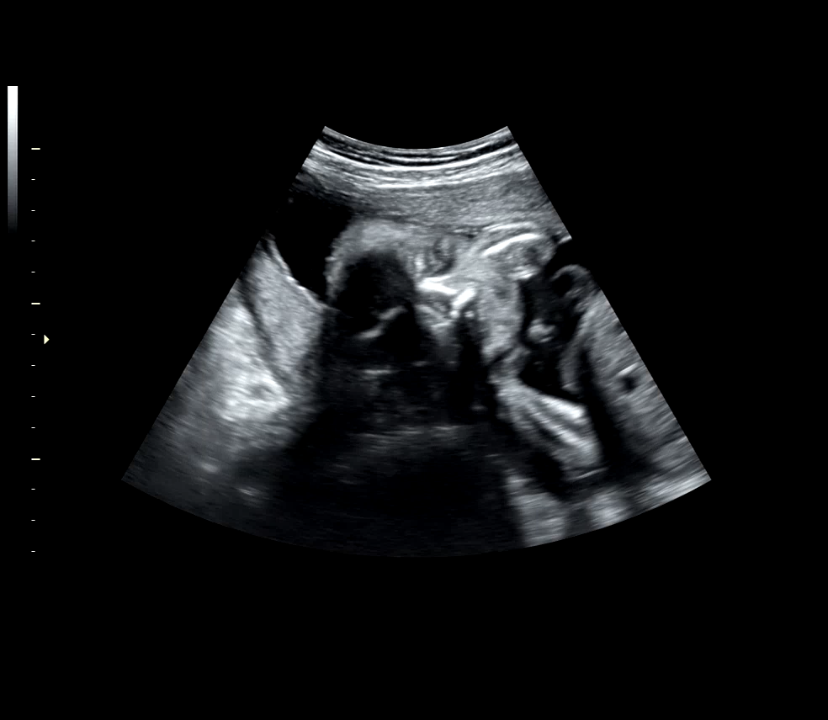

12주차 / 16주차 / 24주차(머리가 낑겨서 좀 좁아보임)